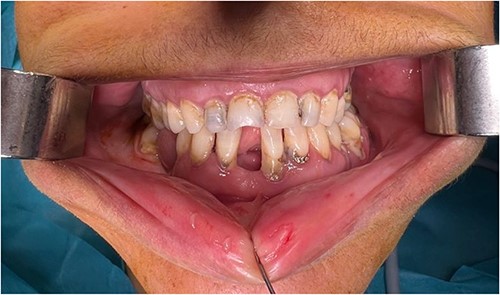

Upon examination, the patient was conscious and stable. The maxillofacial evaluation showed left periorbital edema and ecchymosis, depression of the malar eminence (Fig. 1), tenderness upon palpation of the four malar articulations, a step-off in the lateral orbital rim, and depression of the zygomatic arch. Ophthalmologic exam was normal, and no paresthesia was noted. Intraoral assessment showed restricted mouth opening and an open crossbite (Fig. 2).